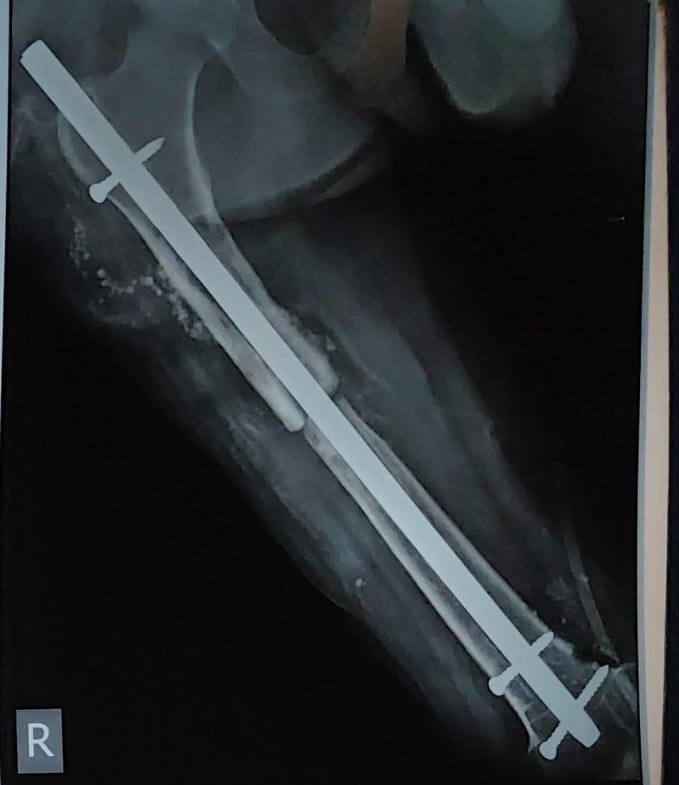

প্রায় দশ বছর আগে দুর্ঘটনায় ডান উরুর হাড় ভেঙেছিল সুকুর আলির । তাঁকে ভর্তি করা হয়েছিল কলকাতা মেডিক্যাল কলেজে । অস্ত্রোপচার করে ফিমার হাড় জোড়া লাগাতে পেরেক জাতীয় বস্তু (নেইল) ও স্ক্রু দিয়ে ধাতব রড বসানো হয় । পরে সুস্থ হয়ে মুম্বইয়ে গিয়ে আবার জরির কাজ শুরু করেন তিনি । কিন্তু মাস কয়েক আগে আবারও ডান পায়ে ব্যথা শুরু হয় তাঁর । প্রথমে ওষুধে সামাল দিলেও হঠাৎ একদিন তিনি লক্ষ্য করেন, পা আর নাড়তেই পারছেন না । তখনই ফের কলকাতা মেডিক্যাল কলেজে গিয়ে এক্স-রে করায় ধরা পড়ে গুরুতর সমস্যা ৷ রিপোর্টে দেখা যায়, কোমর থেকে হাঁটু পর্যন্ত বসানো দীর্ঘ ধাতব রডটি ভেঙে চার টুকরো হয়ে গিয়েছে । সেই কারণেই পায়ে আর জোর পাচ্ছিলেন না তিনি ।

অপারেশনের আগে যন্ত্রটি অটোক্লেভে জীবাণুমুক্ত করা হয় । তারপর সেই যন্ত্র ব্যবহার করেই সফলভাবে সুকুরের উরু থেকে ভাঙা রডের চারটি অংশ বের করে আনেন চিকিৎসকেরা । দীর্ঘদিন ধাতব রড ও হাড়ের ঘর্ষণে তৈরি হওয়া ধাতব যৌগও অপসারণ করা হয় । পরে নতুন নেইল ও স্ক্রু বসিয়ে পুনরায় উরুর ভাঙা হাড়ে ধাতব রড বসানো হয় । প্রায় তিন ঘণ্টা ধরে চলে অস্ত্রোপচার ।